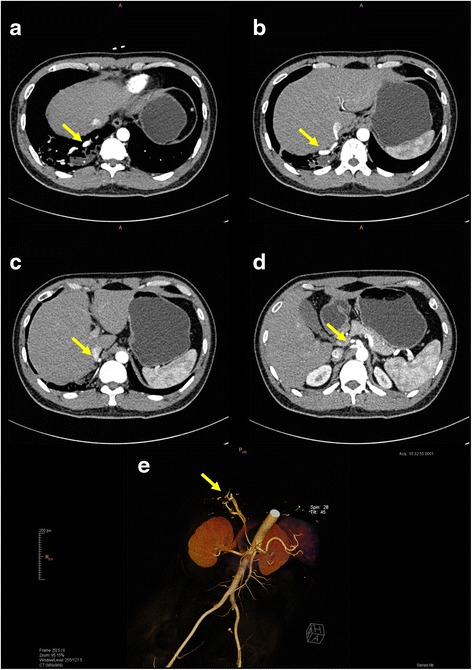

Fig. 2.

CT scanning with IV contrast confirmed the diagnosis of right lower lobe pulmonary sequestration by clearly demonstrating the aberrant feeding vessels (yellow arrows). a-d The entire course of the vessels from the abdominal aorta to the right lower lobe can be traced. e Detailed visualization from 3D reconstruction facilitates pre-operative planning